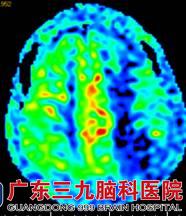

入院后医生查体,刁先生的语言不够流利,张口有限制,颅脑MRI提示:1.左侧额顶叶多发软化灶形成伴胶质增生、局限性脑萎缩,待排部分皮层层状坏死可能;2.双侧基底节-放射冠区、双侧丘脑、左侧半卵圆中心多发陈旧性腔梗灶;3D-ASL提示:左侧额顶枕叶呈低灌注;颈动脉彩超提示:双侧颈动脉粥样硬化(软斑);斑块造成左侧颈内动脉起始段重度狭窄。DSA提示:左侧颈内动脉起始部重度狭窄,狭窄率约80%。

图 2 术前3D-ASL提示:左侧额顶枕叶呈低灌注;